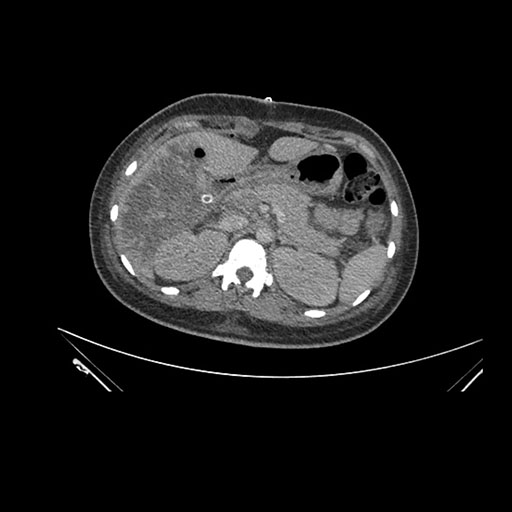

Axial Arterial

Axial Venous

Imaging analysis

Based on initial findings, which issue(s) would you be most concerned about?